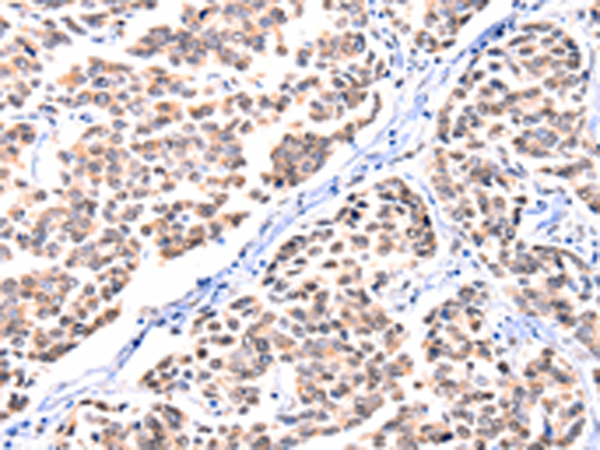

分类: 科研抗体货号: P10851别名: EVEC; UP50; ADCL2; ARMD3; DANCE; ARCL1A; FIBL-5; HNARMD应用: IHC反应种属: Human, Mouse, Rat